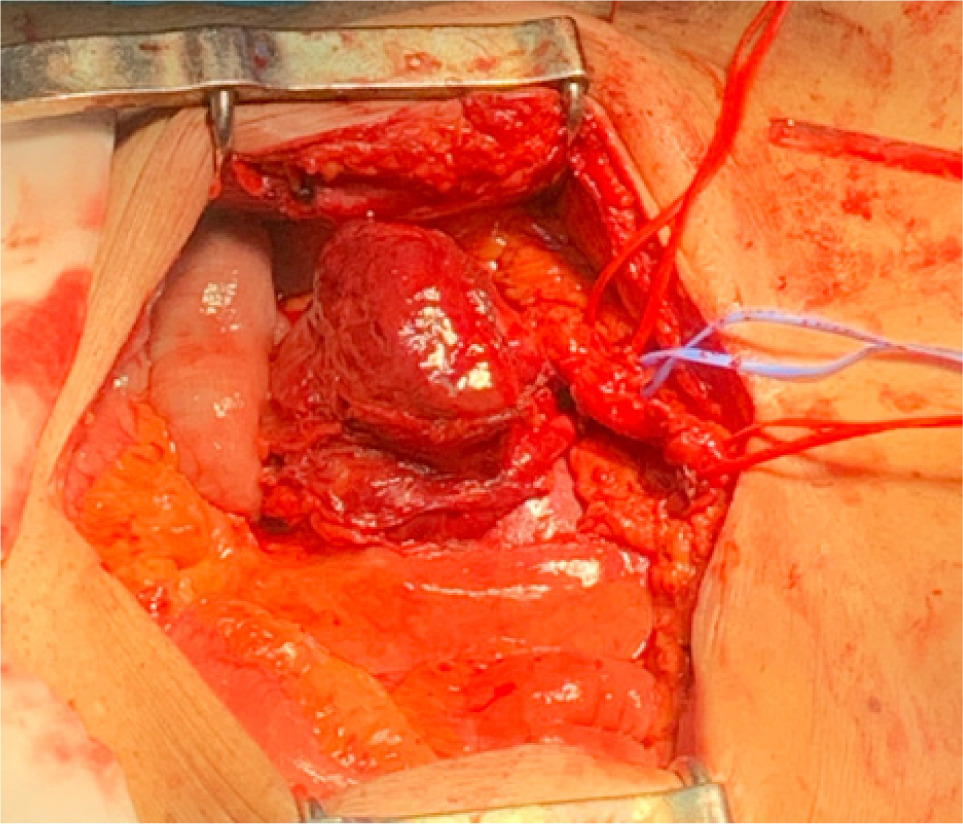

Bilateral RP and ureteric catheterization were first performed for the identification of the hila and calyces of the HSK (Figures 4 & 5). A lower midline laparotomy was performed. The tumor was identified, measuring 7 cm in diameter (Figure 6). Careful dissection of complex hilar structure was performed. Two renal arteries and two renal veins supplying the right side were identified and slung (Figure 7). The tumor was resected with artery clamping (Figure 8). The right lateral calyx of the pelvicalyceal (PC) system was involved and resected. The PC system was closed with 3/O PDS. Renorrhaphy was completed with 3/O V-Loc, and parenchyma was closed with 2/O V-Loc. Ischemic time was 20 minutes, and total operation time was 332 minutes. Blood loss was 420 mL. The patient had completed 1 week of levofloxacin and was discharged on postoperative day 6 with one kick of fever that spontaneously subsided.

Figure 6: Tumor before resection.